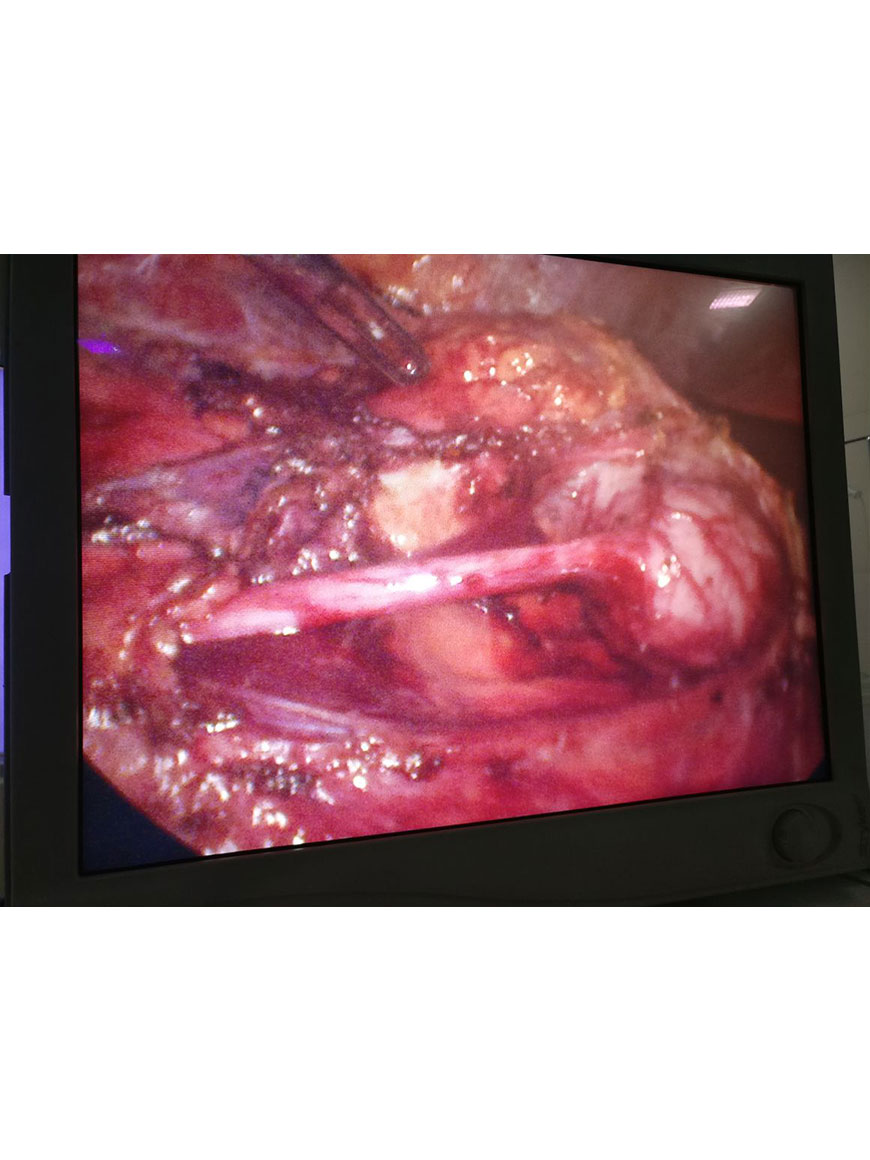

Urethroplasty for PFUDD